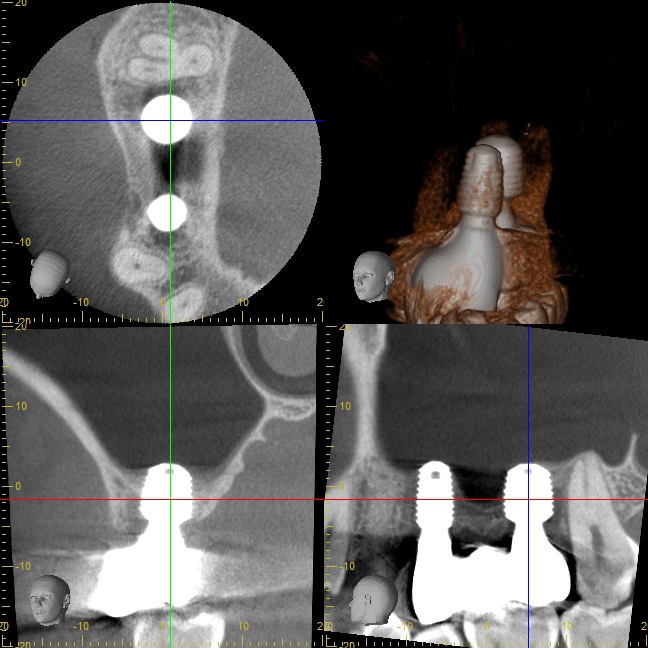

オペ後のCT写真

インプラント先端が少しだけ上顎洞(副鼻腔)に突き出てるように見えますが、問題はありません。

ご自分の骨で持ち上げられたスペースには血液がたまり、少しずつ骨に置換していきます。

治療後のCT写真

インプラント周囲に健全な骨が再生されています。

上顎洞粘膜をDensah® Burでリフトアップした部分にも緻密な骨が再生されました。